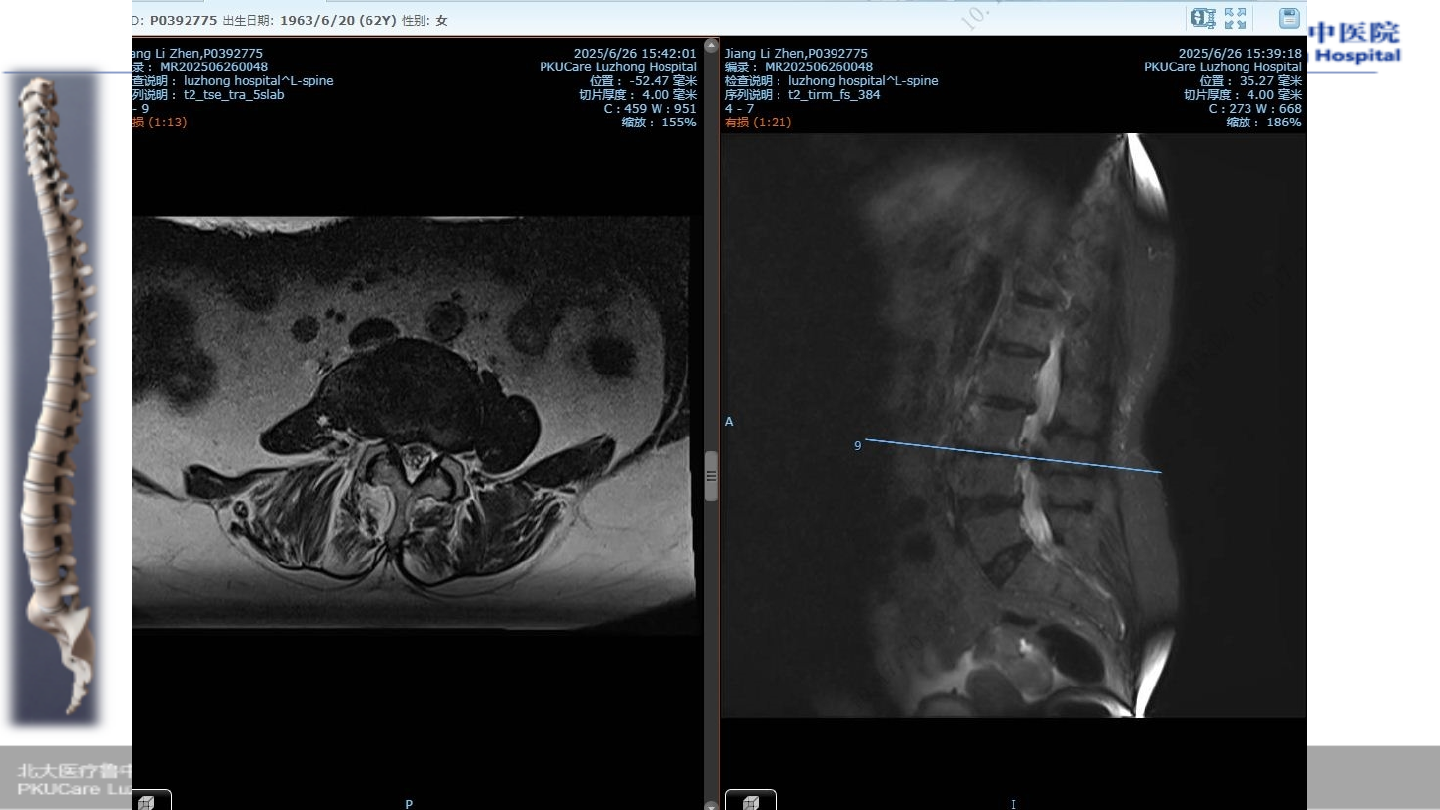

患者:姜某 女性,

67

主诉:

腰疼伴活动受限

2

症状:腰痛,活动后疼痛明显,跛行约

30

Oswestry

功能障碍指数(

ODI

):

85%

VAS

7

既往史:心脏起搏器植入史;焦虑症

病例

1

术前腰椎

MRI